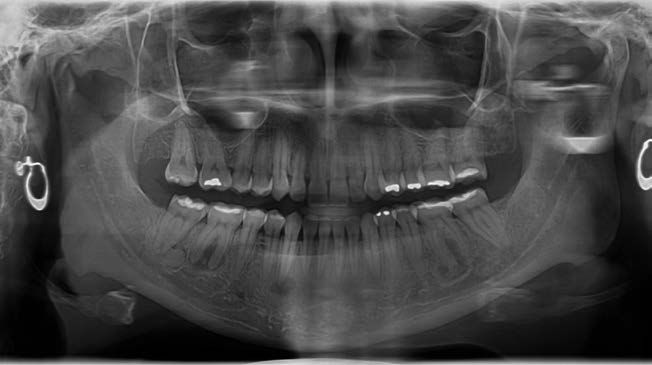

En una radiografía panorámica del año 2018 (Figura 1) se observaron lesiones difusas en la mandíbula, localizadas en las regiones periapicales de los dientes 36, 43, 46 y 47. Estas lesiones presentaban un predominio de áreas radiotransparentes, con la presencia de pequeñas zonas de material radiodenso.

En la radiografía panorámica de 2021 (Figura 2) se evidenciaba una progresión significativa de la lesión, caracterizada por un aumento en la aposición de material radiodenso, especialmente en el cuarto cuadrante. La paciente permanecía asintomática en el momento de la evaluación. Se estableció el diagnóstico de DCOF y se optó por una conducta terapéutica expectante, con controles periódicos cada 6 meses.

En el presente caso clínico, en 2018 se observaron lesiones proliferativas e inmaduras con una apariencia radiotransparente. En etapas más avanzadas de maduración, se identificaron masas radiodensas en las radiografías panorámica realizadas en 2021 y 2023. Estas masas hiperdensas, localizadas en las regiones de los dientes 36, 46, 47 y 43, estaban rodeadas por un área hipodensa y adheridas a las raíces de los dientes correspondientes. Las lesiones estaban bien delineadas del hueso circundante. Muchos autores han informado la presencia de un borde radiotransparente circundante característico y distintivo en la DCO13.